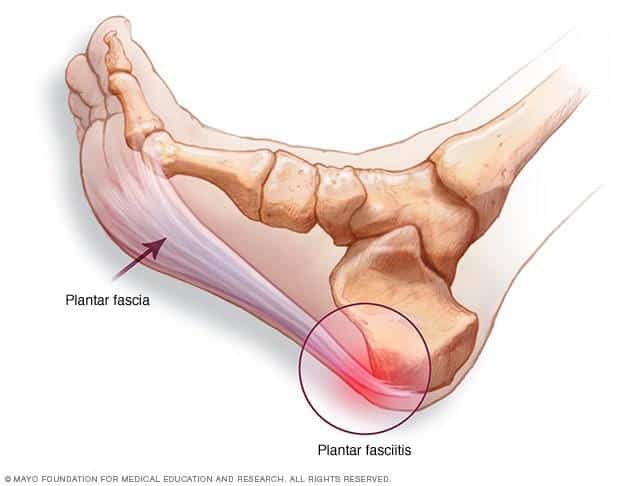

The plantar fascia runs along the length of the sole of the foot and along with various ligaments and muscles of the foot, functions to assist in maintaining its inner arch (like the string of a bow, with the bones of the foot being the bow itself).

Plantar fasciitis is an inflammation of the origin of the fascia at the calcaneus (heel bone). It is a result of a repetitive strain/tear and repair of the fascia from traction forces that have worn it out. It can be likened to an elastic band that has been left out in the sun and stretched too many times; it looses its stretch and has many micro-tears in it.

Heel spurs have long been associated with heel pain, and were originally thought to be its cause. Heel spurs occur at the origin of the flexor digitorum brevis muscle, which lies just beneath  the plantar fascia. However, heel spurs are not often the cause of heel pain associated with plantar fasciitis but can be locally inflamed or even fracture.